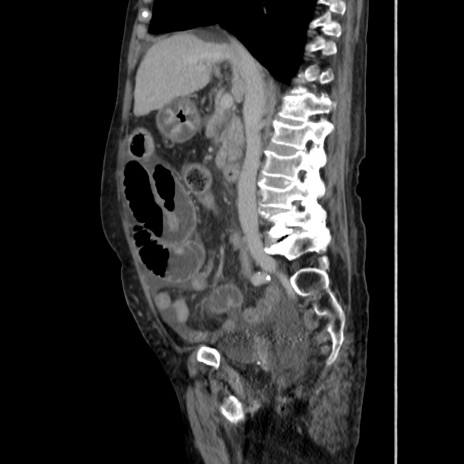

横断像

【症例】80歳代 女性

【主訴】腹部膨満感

【現病歴】他院にて肝硬変にてフォロー中。1週間前から便秘、腹部膨満感、臍部腫瘤あり受診となる。

【既往歴】肝硬変

【身体所見】腹部膨隆あり、皮膚変化なし、疼痛なし。

【データ】WBC 4600、CRP 0.25